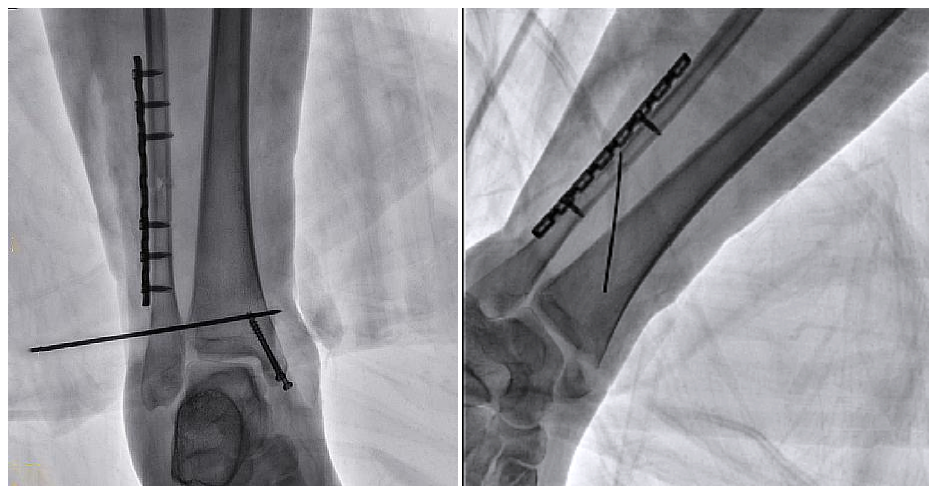

病例2 踝关节骨折复位(31岁)

在踝关节骨折复位手术中,用三维C可以更好地观察骨折部位的复位情况:

正侧位影像观察胫腓联合复位良好

从三维影像看,复位欠佳,贴合度不够